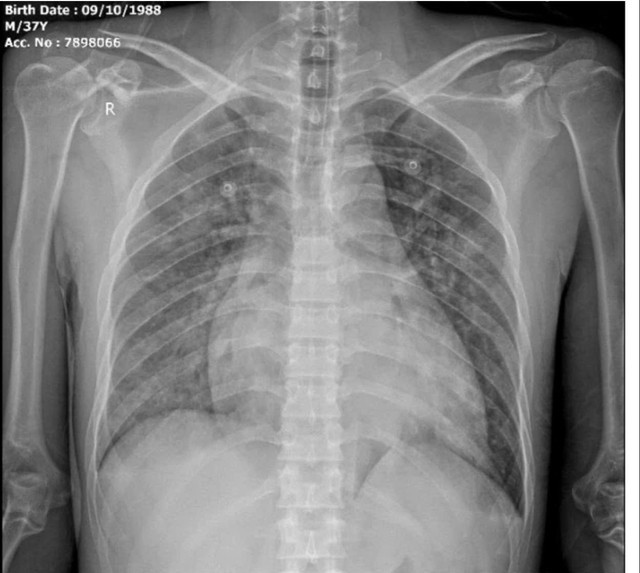

Cấp cứu thành công ca tăng kali máu nguy kịch, nguy cơ ngừng tim. Ảnh SKĐS

Người bệnh là anh Vi Văn T. (37 tuổi, trú tại xã Tiền Phong, tỉnh Nghệ An), có tiền sử bệnh thận mạn giai đoạn cuối, đang lọc máu chu kỳ nhưng đã bỏ chạy thận khoảng 10 ngày trước khi nhập viện. Khi vào viện, người bệnh trong tình trạng nguy kịch với biểu hiện khó thở dữ dội, ho khạc bọt hồng, phù phổi cấp.

Kết quả xét nghiệm cho thấy nồng độ kali máu tăng rất cao (K⁺ = 9,21 mmol/L), kèm theo biến đổi điện tim rõ rệt - dấu hiệu báo động nguy cơ rối loạn nhịp và ngừng tim đột ngột. Các bác sĩ chẩn đoán xác định: tăng kali máu mức độ nặng, phù phổi cấp, suy tim trên nền bệnh thận mạn giai đoạn 5.